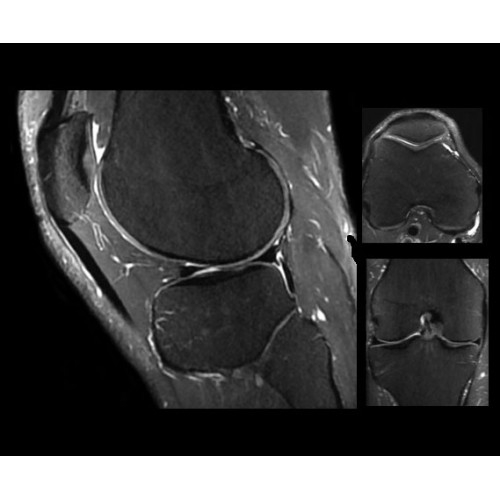

SIGNA PET/MR 3.0T — это гибридная система, в которой совмещаются две принципиально разные технологии — магнитно-резонансную томографию (МРТ) и позитронно-эмиссионную томографию (ПЭТ). Система отличающийся высокой чувствительностью и эффективностью и предназначена для диагностики в области онкологии, неврологии, кардио-васкулярных исследований, исследований воспалительных процессов.

Компания GE Healthcare представляет революционную, полностью интегрированную систему SIGNA PET/MR1, в которой сочетаются времяпролетная технология (TOF) и возможности напряженности магнитного поля 3.0 Тл. Мы поможем вам поднять исследования на более высокий уровень. SIGNA PET/MR позволяет достичь впечатляющей точности и скорости исследований, а благодаря новейшей технологии реконструкции Q.Clear2 качество изображений улучшается в два раза. Кроме того, в систему включен полный набор клинических приложений и гибких катушек для проведения любых видов исследования, открывая для вас возможности визуализации, о которых вы даже не догадывались.

Кроме того, в результате использования технологии TOF и инновационной технологии реконструкции Q.Clear вы сможете добиться прекрасного соотношения сигнал/шум. А благодаря технологии нулевого времени эхо (ZTE) визуализировать костную структуру без ионизирующего излучения. Все эти разработки для улучшения качества сканирования и точности анализа помогут вам использовать весь потенциал ПЭТ/МРТ.

Впечатляющие клинические возможности

Система SIGNA PET/MR предлагает впечатляющие клинические возможности и открывает доступ к наиболее полным пакетам программных приложений.

• Q.Clear — в основу технологии легли накопленные знания о том, как минимизировать помехи при реконструкции и получить четкое изображение. При значительном улучшении качества изображения сохраняется точность расчетов. Сочетание технологии TOF и реконструкции Q.Clear — ваш надежный помощник для получения точных и достоверных данных.

• МРТ с функцией нулевого времени эхо (ZTE) отличается точностью, возможностью персональных настроек и отсутствием ионизирующего излучения. Она приходит на смену традиционному исследованию на основе рентгеновского излучения. МРТ с функцией нулевого времени эхо (ZTE) на базе SIGNA ПЭТ/МРТ является более надежной и быстрой по сравнению с системами, использующими сверхмалое время эхо (UTE).